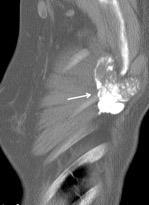

Nódulo en língula.

Cirugía de Ca .de mama hace 23 añosedema de brazo y ganglio en axila. ¡Metástasis!.